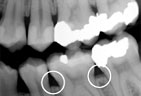

Periodontitis Periodontitis